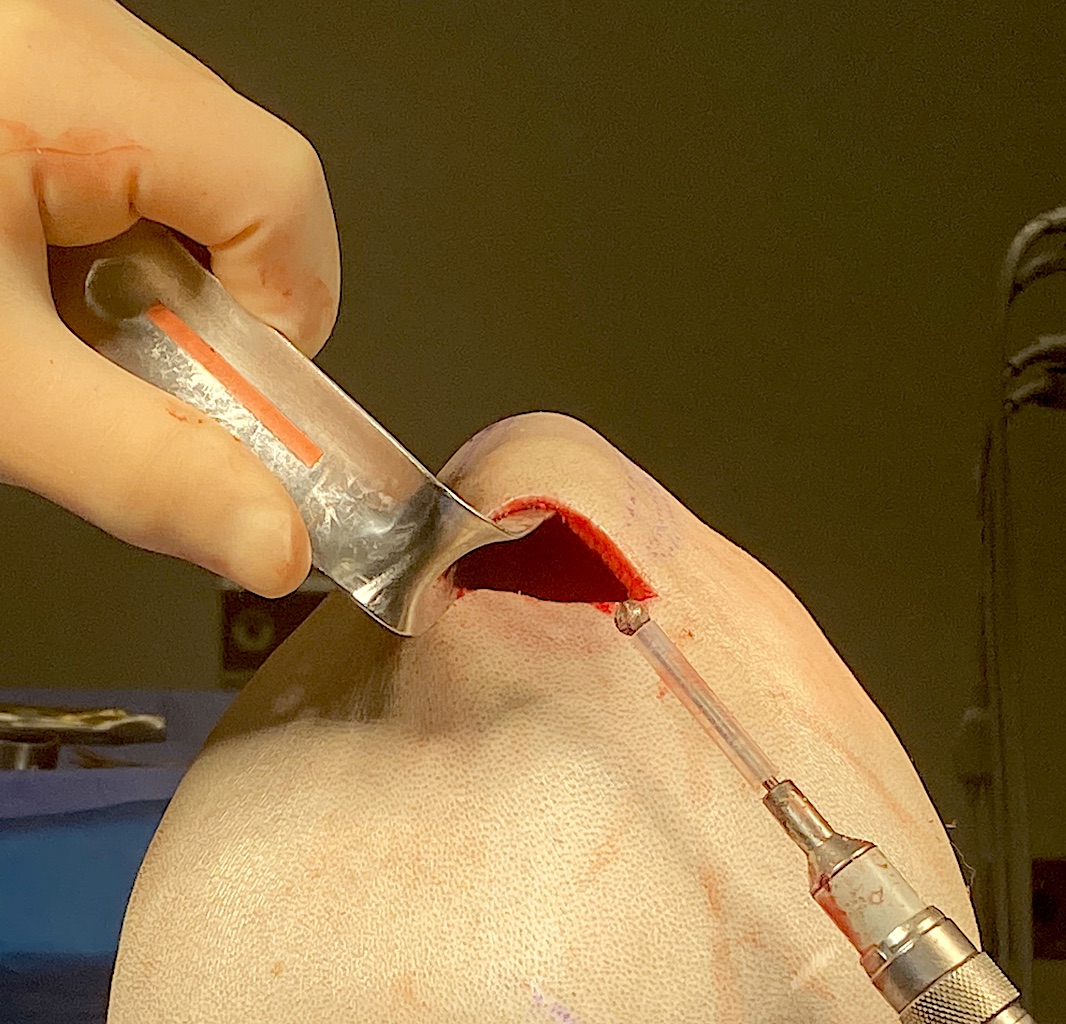

Desire for change of head shape from front view form an inverted V shape to a rounder and wider head shape.

Placement of custom extended forehead-temporal implants through incisions in the crease behind the ear. (he had a prior back of head skull implant which is green in the implant designs and which the head widening implants partially covered it)

Desire for change of head shape from front view form an inverted V shape to a rounder and wider head shape.

Placement of custom extended forehead-temporal implants through incisions in the crease behind the ear. (he had a prior back of head skull implant which is green in the implant designs and which the head widening implants partially covered it)